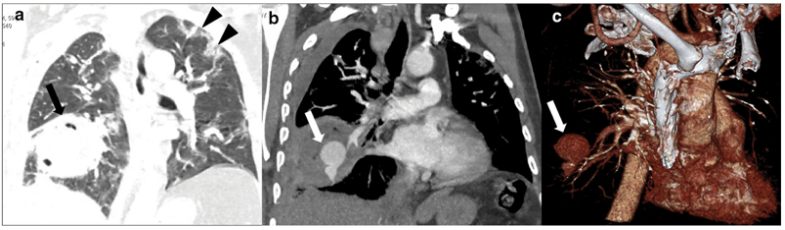

糖皮质激素的使用在其他病种中也被认为是IPA的危险因素,在重症流感中也不例外,有研究表明入ICU前系统性应用大剂量糖皮质激素是继发IAA的独立危险因素。除了重症流感,患者可能还会合并其他基础疾病,尤其是可以影响患者免疫状态的基础疾病,可能也是IAPA的危险因素。病例1::男,15岁,学生;主因“发热、干咳16天,加重伴呼吸困难8天”入院。既往体健,无基础病。入中日医院MICU时间为2018年1月16日,死亡时间为2018年1月26日。患者16天前(2017年12月30日)出现发热,体温39.0℃,伴干咳、咽痛。8天前(2018年1月7日)出现呼吸困难。血气分析示Ⅱ型呼吸衰竭,WBC 24.1×109/L,NE% 90%,PCT 3.3 ng/ml。不断升级抗细菌治疗,效果不佳:头孢曲松→亚胺培南、阿奇霉素、利奈唑胺。7天前(2018年1月8日)确诊乙流,加用帕拉米韦+奥司他韦。2天前(2018年1月13日):血GM试验测值增高,痰培养烟曲霉,诊断IAPA,加用伏立康唑。2018年1月15日转入中日医院呼吸与危重症医学科MICU。2018年1月8日胸部CT(起病1周余)提示气压伤非常严重,以及沿气道分布的斑片和小结节。此时的影像学提示曲霉感染已经显而易见(图1),但尚未得到病原学证据的支持,因此外院当时并未予抗真菌治疗,延迟抗真菌治疗也是导致患者预后不良的重要原因之一。1月15日(转入中日医院MICU后)气管镜检查,镜下可见气道狭窄和黏膜充血水肿均较明显,表面大量白苔,触之易出血(图2)。此时除了曲霉感染,BALF病原学还发现合并了CRAB感染。患者影像学快速进展,1月15日胸部CT显示双肺弥漫性沿支气管血管束分布的结节影、斑片影、厚壁空洞及片状实变(图3)。1月22日胸部CT显示双肺病变明显进展,结节、斑片融合为大面积实变影(图4)。最终患者因CRAB血流感染导致感染性休克,后期又并发脓毒性心肌病,最终去世。病例2::女,65岁,退休。间断干咳伴发热10天,加重伴呼吸困难4天。既往2型糖尿病史35年,使用精蛋白生物合成人胰岛素注射液(预混30R)治疗,血糖波动在7~8 mmol/L。患者入ICU时间为2018年2月4日,出ICU时间为2018年4月19日。10天前(2018年1月25日)“感冒”后出现干咳,伴发热,体温最高37.8℃。7天前(2018年1月28日),血常规:WBC 12.49×109/L,NEU% 87.5%,LYM% 7%,予莫西沙星。1月30日复查血常规:WBC 23.88×109/L,NEU% 91.5%,LY% 4.6%,调整抗生素为头孢噻肟+莫西沙星。4天前(1月31日)呼吸困难加重,SpO2(未吸氧)88%,复查血常规:WBC 37.04×109/L,NEU% 93.7%,LYM% 1.7%,PCT 1.79 ng/ml,痰涂片可见真菌孢子及菌丝。3天前(2月1日)咳痰费力,SpO2降至71%,开放气道吸痰过程中心率降至32次/min,立即心肺复苏,气管插管球囊辅助通气,约12 min患者自主心率恢复,接呼吸机辅助呼吸,经气道可吸出大量黄色黏痰,痰流感病毒核酸阳性。1月31日胸部CT示:沿支气管血管束分布的斑片和实变影(图5)。气管镜下可见充血、水肿,曲霉特征性假膜相对较少(图6)。